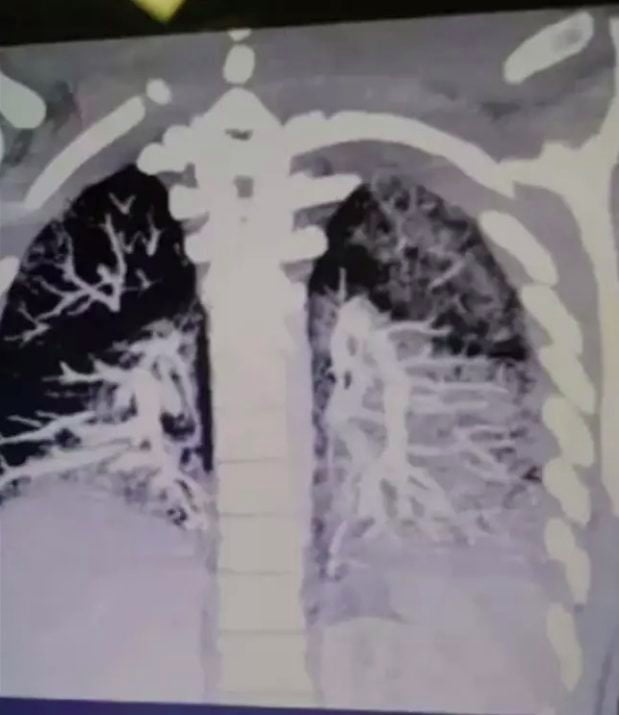

Sähkötupakkaa polttaneen pojan isä jakoi karmivan röntgenkuvan: ”yli 60-vuotiaan keuhkot”

Perheenisä jakoi karmivat röntgenkuvan teinipoikansa keuhkoista, jotka olivat täynnä öljyä. Perheenisän mukaan öljy on peräisin sähkötupakasta.

Lääkärit olivat sanoneet Anthonylle, että hänellä on 60-vuotiaan, kaksi askia päivässä polttavan henkilön keuhkot ja että keuhkoihin muodostuneet arvet ovat pysyviä.

”Neste on muuttunut kiinteäksi. Se on peittänyt hänen keuhkojensa sisäpuolen. Lääkäreiden mukaan keuhkoihin joutuva kosteus ei ole hyvä asia… Jos keuhkoihin menee öljyä ja kosteutta niin syntyy nopeasti ongelmia”, Keith kertoo.

Lääkärin mukaan keuhkoihin joutunut kiinteä aines muistutti hieman pekonin rasvaa, joka kovettuu jäähtyessään. Kuulostaa ihanalta!